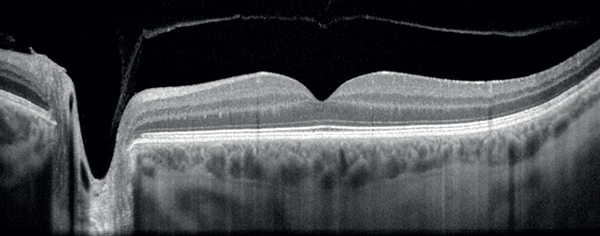

Revo OCT

OCT Scans

High quality cross-section scans that capture the finest details for early disease detection.